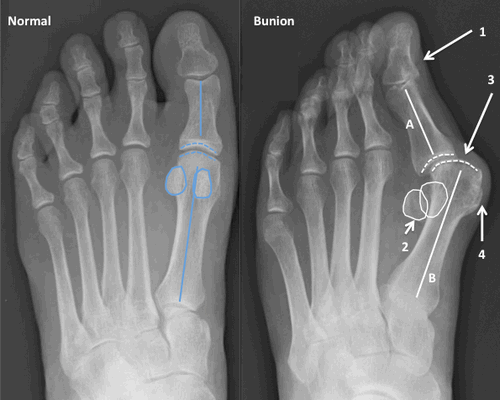

По статистике, Hallux Valgus разной степени выявляют у 100% пациентов с поперечным плоскостопием. Во время хирургического вмешательства врачам приходится одновременно устранять обе патологии.

Что такое вальгусная деформация? Вначале Hallux Valgus вызывает искривление только большого пальца стопы. В результате у человека увеличивается нагрузка на головки 2-4 плюсневых костей, что ведет к молоткообразной деформации II-V пальцев. Своевременное хирургическое лечение помогает избежать этого неприятного явления.

Z-образная остеотомия Scarf - это золотой стандарт лечения вальгусной деформации. Она позволяет установить головку плюсневой кости под нужным углом. В ходе хирургического вмешательства врачи также убирают деформацию суставной капсулы и меняют направление некоторых сухожилий.

Важно! У большинства пациентов с вальгусной деформацией врачи выявляют костную мозоль (экзостоз). Нарост локализуется на медиальной поверхности головки I плюсневой кости. Как правило, его удаляют во время всех операций, в том числе и малоинвазивных.

Не путайте спиливание костного нароста с остеотомией. Это две совершенно разные манипуляции. Цель первой - убрать косметический дефект, второй - восстановить нормальное функциональное состояние стопы. Помните, что удаление костной мозоли (операция Шеде) не в состоянии излечить вас от Hallux Valgus.